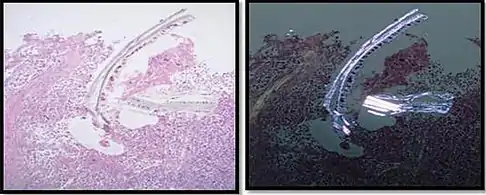

Cellulose contamination, in H&E stain and polarized light

Cellulose contamination, in H&E stain and polarized light Cardiac muscle (bottom) with contamination from thyroid tissue (center)

Cardiac muscle (bottom) with contamination from thyroid tissue (center) Crush artifact from compression by forceps on the tissue sample

Crush artifact from compression by forceps on the tissue sample Folding artifacts (white arrows) and a crush artifact (black arrow, with cytoplasmic hypereosinophilia and nuclear pleomorphism) from a needle.

Folding artifacts (white arrows) and a crush artifact (black arrow, with cytoplasmic hypereosinophilia and nuclear pleomorphism) from a needle.